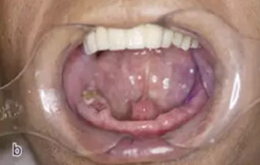

從圖1可以看出患者缺牙區(qū)的間隙充足,牙齦健康,頰側(cè)軟組織略有凹陷。

圖1 缺牙區(qū)的頰側(cè)和口內(nèi)照片